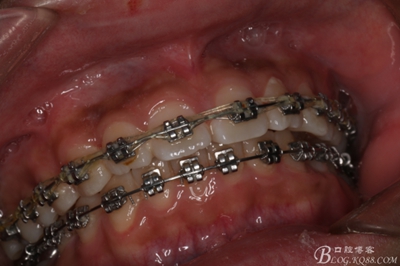

患者、王xx、男、15歲。主訴:口腔正畸矯治即將結(jié)束,要求拔除阻生牙?,F(xiàn)病史:一年前,患者在個體門診做正畸治療,治療經(jīng)過不詳。今來我院,要求拔除阻生下頜第三磨牙,以便矯治第二磨牙??谇粚?茩z查:上下頜固定矯治器。牙列基本排齊。37和47近中阻生,38和48未萌出,x光檢查:38、48牙冠已經(jīng)形成,牙冠方向為水平位,37、38近中位萌出。治療方案:建議拔除38、48.并通過正畸裝置直立37、47.患者家屬同意治療方案,簽知情同意書。

圖2.術(shù)前的口內(nèi)閉口位照片:上下牙列基本整齊

圖3.術(shù)前左側(cè)下頜口內(nèi)照片:37近中阻生,38口內(nèi)看不到。